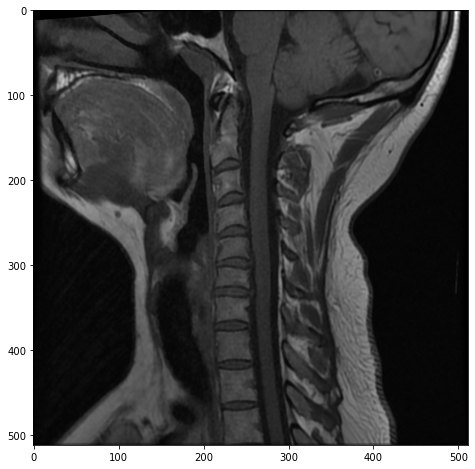

plt.figure(figsize=(8, 8))

plt.imshow(mri[14, :, :], cmap="gray")

<matplotlib.image.AxesImage at 0x11351e2b0>

Here, as we move out to the side of the patient’s neck, we can see the MRI catching their side teeth in the top left, as well as more of the patient’s neck muscles.